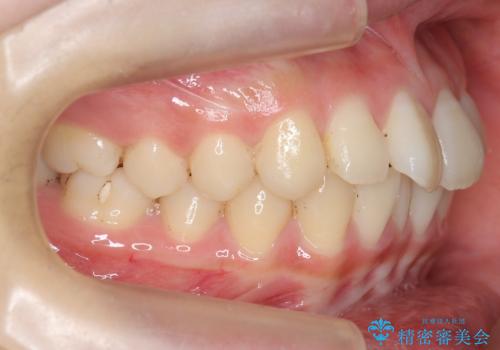

前歯のがたつき 部分矯正でコストダウンしながら、かみ合わせも治療

- 前歯のがたつきを気にして来院。

左下の小臼歯が捻転し、反対咬合になっていました。

先にワイヤーで部分矯正を行ってから、インビザラインの部分矯正を行いました。

先に難しい部分をワイヤー矯正することで、インビザラインの部分矯正コースで短期間で予算も抑えて確実に治すことができます。